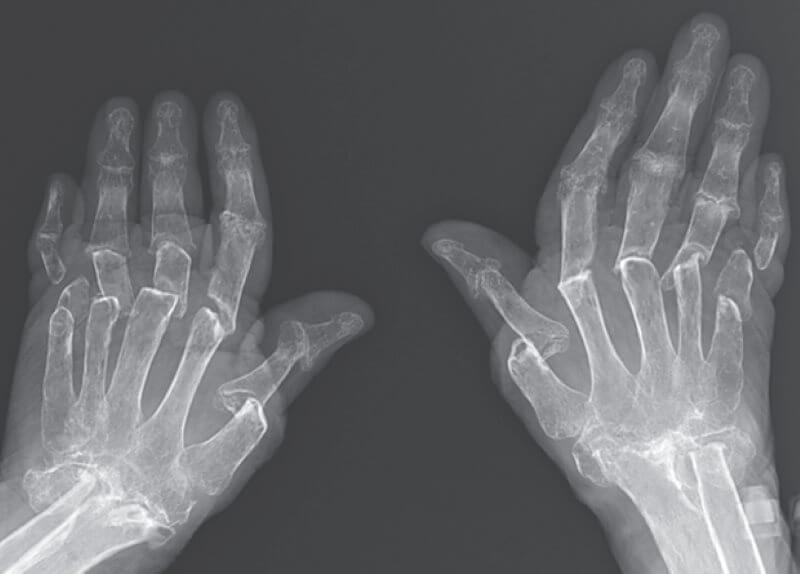

Но больше всего докторов удивило то, что пальцы пациентки были заметно укорочены. Однако, если потянуть за фаланги пальцев, они начинали вытягиваться до нормальной длины. Чтобы выяснить причину такого явления пациентку направили на рентген, который впоследствии и дал ответ на интересующий докторов вопрос. Оказалось, что осложнившийся артрит сильно разрушил фаланги пальцев, вследствии чего кости и суставы стали короче, а кожа и связки остались такого же размера. Именно из-за этого пальцы пожилой женщины и стали сжиматься и вытягиваться как подзорная труба.

Рентгеновский снимок рук пациентки